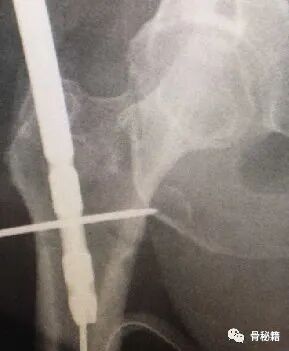

4.这种情况下就可以在复位加压的情况下完成骨折的扩髓和固定了

5.最后再通过螺钉的加压完成最后加压

术后影像,是不是感觉不错呢??